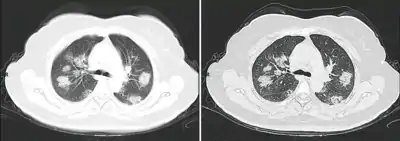

Dégâts pulmonaires

Les études en microscopie électronique et sur coupes histologiques de tissus pulmonaires (faites après autopsies) ont montré que les virions sont dans le poumon essentiellement localisés dans les pneumocytes[200].

Comme dans le cas du SARS, puis du MERS, la Covid se traduit dans l'arbre respiratoire par des lésions alvéolaires diffuses, caractérisées par des phases exsudatives et prolifératives de ces lésions, avec une congestion des vaisseaux capillaires et une nécrose systématique des pneumocytes, et très souvent une atteinte des membranes hyalines, un œdème interstitiel et intra-alvéolaire.

Les autopsies ont aussi révélé de fréquents événements thromboemboliques (« parfois cliniquement insoupçonnés au décès »)[201]. Outre une hyperplasie pneumocytaire de type 2, on a souvent observé une métaplasie squameuse avec atypie et micro-thrombus plaquettaire-fibrine[200],[202],[203],[204],[205].

L'infiltrat inflammatoire est toujours majoritairement composé de macrophages, souvent présents dans la lumière alvéolaire, souvent accompagnés de lymphocytes dans l'interstitium[200]. Des membranes hyalines se forment fréquemment, et une hyperplasie atypique des pneumocytes est également fréquemment constatée post-mortem. Le thrombus plaquettaire-fibrine des petits vaisseaux artériels peut être relié à une coagulopathie apparemment fréquente chez les malades de Covid-19 et qui selon Carsana & al (2020) devrait être l'une des principales cibles du traitement[200].